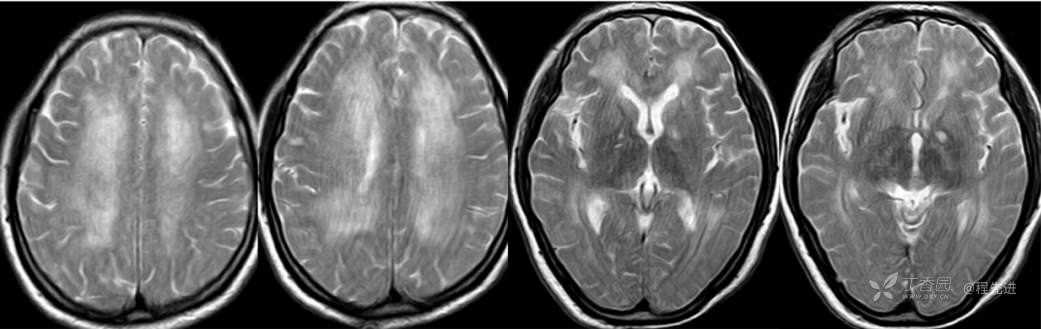

T2